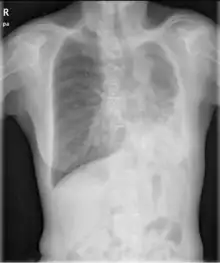

- Chest X-ray is effective in detecting the traits of lung herniation.[1] The unaffected side of lung tends to undergo hypertrophy, and move towards the empty space in the chest wall on the opposite side.[1] This herniation could be indicated by fluoroscopy.[1] With age increasing, the herniation progresses and ease its detection.[1]

- Electrocardiogram is useful in detecting dextrocardia, a possible outcome when agenesis is present on the right lung.[1] With empty space in the chest wall, the heart rotates in clockwise direction, shifting the location for apex beat occurrence.[1] Hence cardiac physical examination also helps as heart sounds is heard best at right chest with dextrocardia.[1][4] In the condition of left side agenesis, heart sounds will appear to be louder than normal.[1][4]

- Chest asymmetry, as a possible trait for pulmonary agenesis, is found to be more obvious in adult patients, especially in males.[4] Breast development in females tends to make it less obvious for the observance of asymmetry, though it could still be indicated by a more conical shape and slightly higher location of the breast on the affected side.[4]